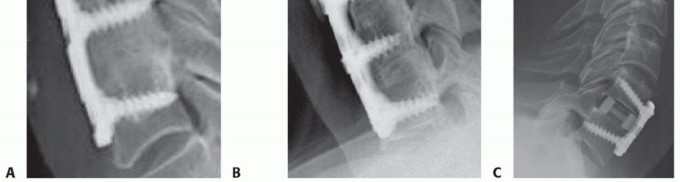

### TECH FIG 6 • Commercially available sizers are used to determine optimal graft size. A trial that fits snugly under gentle Caspar distraction will suffice. If autograft is used, the appropriate trial is used as a template for cutting the autograft bone. The surgeon should try to place a graft that fills the space as much as possible without overdistracting, which can cause posterior neck pain, or entering the spinal canal. We generally prefer to use commercially prepared cortical allografts for ACDF, except in patients with poor healing potential. Alternatively, autograft iliac crest bone can be used. ### Determining Plate Length Plating is optional for one-level ACDF with autograft. If allograft or multilevel surgery is performed, plating is recommended. Once the graft has been placed, the size of the plate is then determined. Optimal plate length is one that allows for the screws to be immediately adjacent to the endplates (TECH FIG 7). This plate length allows for screws that angle away from the disc space, which in turn allows for screws that are longer than ones directed parallel to the disc space, yet are short enough to avoid entry into the supra- and infraadjacent disc spaces. This length also prevents impingement of the plate into the adjacent disc spaces. ### Plating Techniques The plate should be contoured into lordosis to lie flush against the vertebral bodies. It should also be centered coronally within the margins of the uncinate processes. Screws should also be angled medially to decrease the chance of lateral injury to nerve roots or vertebral arteries.

### TECH FIG 7 • Proper plate sizing. A. The length of an optimally sized plate is such that the screw holes at the top and bottom of the construct are immediately adjacent to their respective endplates. In this example, even though this was done, the plate is still closer to the cephalad adjacent disc space than ideal because the vertebral bodies in this patient are relatively short. Nevertheless, adjacent-level disc degeneration did not occur in this patient at 2-year follow-up. Bicortical screw purchase is not routinely needed, but estimates of screw length can be obtained by measuring MRI or CT scans preoperatively. Screws should be angled away from the disc space to provide greater length and divergent fixation, which may better resist pullout. B. In another patient with short vertebrae who presented to us with adjacent level disease, the plate was placed too close to the adjacent disc, resulting in adjacent-level ossification disease (arrow). The cephalad screws are not immediately adjacent to the endplate but rather inserted at roughly the midpoint of the vertebral body. Similarly, the caudal screws begin in the midportion of the vertebral body. The plate is too long distally and comes close to the subjacent disc as well. As demonstrated by these examples, proper plate sizing is especially important in patients with shorter vertebrae where the adjacent discs are closer together. C. Screw fixation and graft carpentry. This patient underwent C6-C7 ACDF for cervical myeloradiculopathy. Because he had a very wide and deep disc space, two bone grafts were inserted side by side and rotated 90 degrees to the usual orientation in order to better fill the disc space, increase contact through the fusion area, and improve load sharing across the construct. Screw lengths were also optimized to improve fixation. The screw length can be estimated preoperatively by measuring the depth of the vertebral body on CT or MRI scans. Ideally, screws are as long as possible within the vertebral body to maximize fixation. Dynamic plates can be used if desired (TECH FIG 8). They have the theoretical benefit of improving load sharing on the graft. There are several types of dynamic plates. Variable screw systems allow for toggling within a fixed screw hole with settling of the construct. A potential downside is that the screw can loosen within bone as toggling occurs. Slotted plates have holes that allow screws to translate longitudinally as the construct shortens. The screws are rigidly fixed to bone and do not toggle, but excessive translation may lead to adjacent-level plate impingement. Telescoping plates use fixed screws in nonslotted holes but the ends of the plate telescope with respect to each other as settling occurs. Postoperative adjacent-level plate impingement will not occur with this design if the plate is properly positioned at the time of surgery, as the distance from the end of the plate to the endplate does not change with construct shortening. However, these plates tend to be somewhat thicker. If dynamic plates are used, the surgeon must perform the plating procedure to accommodate the anticipated settling without overlapping uninvolved adjacent discs.8 In general, we prefer rigid plating in most cases to avoid excessive construct settling. Variable plating has not been clearly demonstrated to improve outcomes or fusion rates. 8